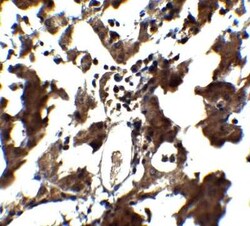

ZEB1 Polyclonal antibody specifically detects ZEB1 in Human samples. It is validated for Western Blot, ELISA, Immunohistochemistry, Immunocytochemistry/ Immunofluorescence, Immunohistochemistry (Paraffin)

| Western Blot, ELISA, Immunohistochemistry, Immunocytochemistry, Immunohistochemistry (Paraffin) | |

| Western Blot 1 μg/mL, ELISA 1:100-1:2000, Immunohistochemistry 5 μg/mL, Immunocytochemistry/ Immunofluorescence 20 μg/mL, Immunohistochemistry-Paraffin 5 μg/mL | |